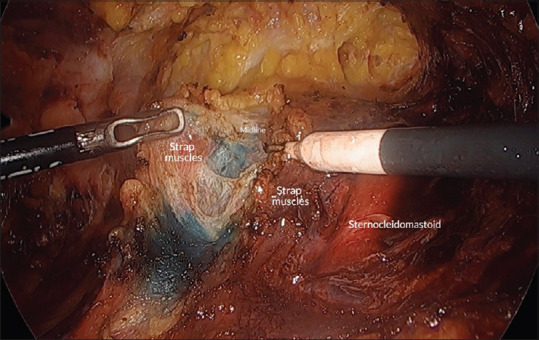

Abstract: Endoscopic thyroidectomy is a minimally invasive surgical approach that has become popular due to its cosmetic advantages and reduced post-operative discomfort. Central to the success of this procedure is the accurate identification of the midline, which becomes a challenge in endoscopic surgeries. We propose a novel method of using methylene blue, a Food and Drug Administration-approved dye, which offers the ability to clearly mark the midline, enhancing orientation and reducing the potential for injury to critical anatomical structures. Although using methylene blue has many benefits, there are drawbacks, including the requirement for intraoperative ultrasonography. Continued research and clinical experience will be critical in improving and extending its use in the field of thyroid surgery.